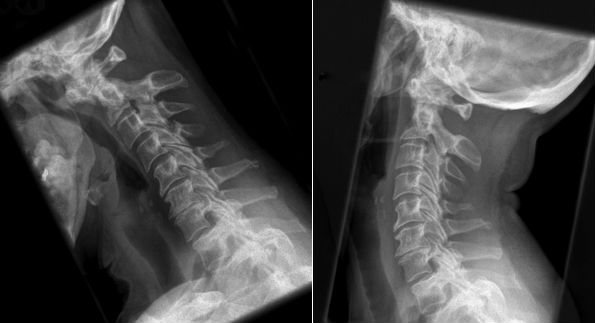

Болезнь обычно появляется в шейном и поясничном отделах. При ретролистезе шейного отдела обычно смещаются третий и пятый позвонок, при поясничном – с первого по пятый.

Во врачебной практике часто встречается заболевание шейных сегментов, потому что этот отдел чрезмерно подвержен травмам. Для этой болезни характерен долгий процесс с дегенеративно-функциональными изменениями, которые приводят к появлению сердечно-сосудистых заболеваний и даже инсульту.

Шейный отдел позвоночного столба состоит их 7 тонких позвонков – C1, C2, C3, C4, C5, C6, C7. Он обладает хорошей подвижностью, поддерживает голову в вертикальном положении и обеспечивает движения шеи. В то же время мышечно-связочный аппарат довольно слабый, что способствует анатомическому смещению позвонков при воздействии неблагоприятных факторов. Наиболее часто встречается смещение пятого шейного позвонка (C5) назад относительно шестого (C6). Патологический процесс приводит к сдавливанию позвоночной артерии и спинномозговых корешков, что вызывает появление характерных симптомов.

Проведение рентгенографии в боковой проекции позволяет обнаружить смещение тел позвонков

При 1 степени болезни клинические проявления слабо выражены и часто объясняются больными усталостью, перенапряжением на работе или стрессом. Однако заболевание постоянно прогрессирует, симптоматика со временем нарастает, что заставляет пациентов обращаться к врачу. Следует помнить: чем значительнее смещение позвонков, тем сложнее лечение и меньше шансов на выздоровление. За медицинской помощью необходимо обращаться при первых проявлениях заболевания, что улучшает его прогноз и предупреждает формирование осложнений.